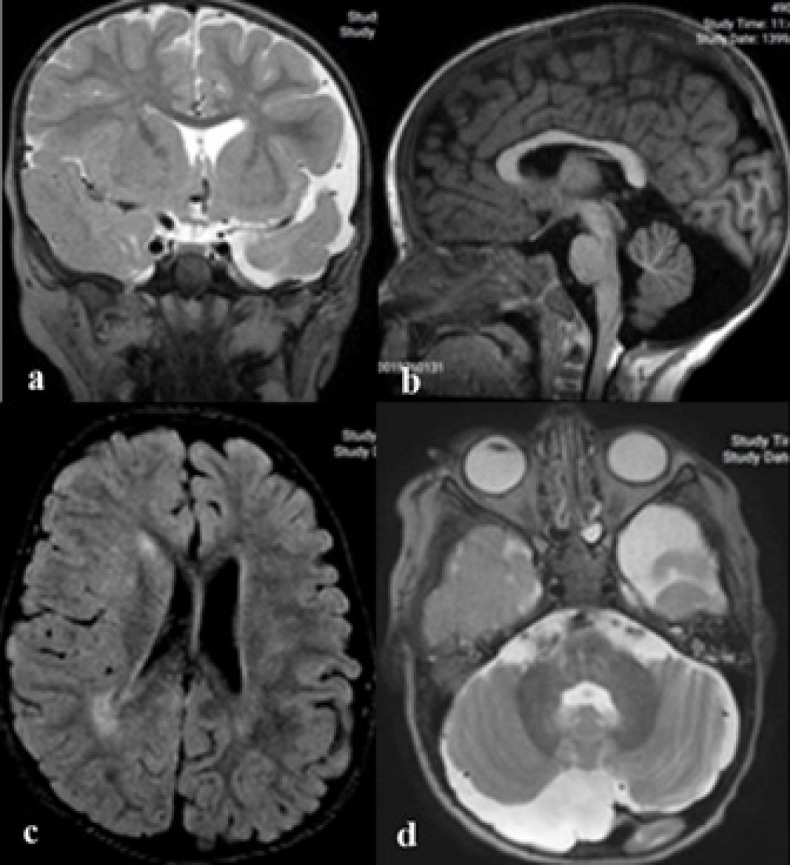

脑皮脂肪瘤病(ECCL),也称为哈伯兰综合征,是一种罕见的、非遗传性的、非进行性的先天性神经皮肤综合征,伴有潜在的外胚层发育不良。该综合征的典型三联征是中枢神经系统(CNS)、眼部和皮肤受累,表现为头皮、颈部和面部的单侧脂肪瘤病变,伴同侧脑异常和同侧眼脉膜瘤。在此,本研究报告一例2岁男童首次出现癫痫持续状态。椎管内脂肪瘤、蛛网膜囊肿、脑偏瘫、不对称脑积水、脉络膜瘤和角膜混浊。本病例符合穆格诊断Haberland综合征的临床标准。此外,本研究还介绍了线状和轮状瘤样黑色素过多症以及脑室周围白质增高作为该综合征的新表现。

Encephalocraniocutaneous lipomatosis (ECCL), also known as Haberland syndrome, is a rare, nonhereditary, nonprogressive congenital neurocutaneous syndrome with underlying ectodermal dysgenesis. The classic triad of this syndrome is central nervous system (CNS), ocular, and cutaneous involvement as unilateral lipomatous lesions of the scalp, neck, and face with ipsilateral brain anomalies and ipsilateral ocular choristoma. Herein, this study reports a case of a 2-year-old boy presented with status epilepticus for the first time. Intraspinal lipoma, arachnoid cyst, cerebral hemiatrophy, asymmetric hydrocephaly, choristoma, and corneal clouding were noted. This case fulfilled Moog's clinical criteria for diagnosis of Haberland syndrome. Additionally, this study introduces linear and whorled nevoid hypermelanosis and cerebral periventricular white matter hyperintensity as novel manifestations of this syndrome.